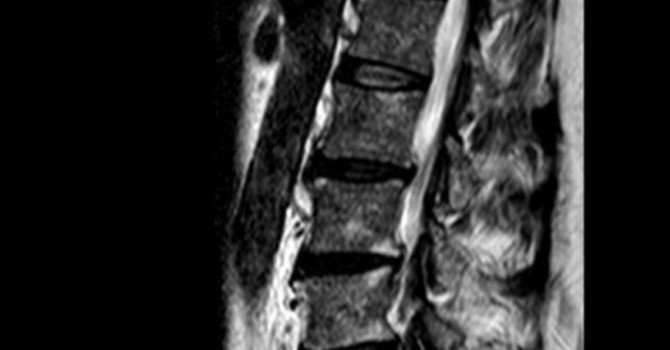

Many personal injuries involve hidden damage that standard imaging might miss, particularly when it comes to the spine. At Clear Life Scoliosis And Chiropractic, we are specialists in spinal ligament injuries. We measure spinal instability utilizing up-to-date evidence-based subluxation identification and management techniques specifically designed for spinal injuries.

Doctors treating an injured patient must be able to accurately and objectively assess and diagnose the full extent of their patient’s injuries.  Without this, patients may get poor recovery results. If the spine is injured, its parts must be deranged.  There are only three types of of spine injuries:

1. Fracture

2. Spinal Instability

3. Disc Herniation

How Does the Spine Work?

Each function, organ and system of the human body is under the direct control of the nervous system.  The brain controls everything in the body.  It sends signals to every part of the body.  These signals travel down from the brain, through the brainstem and spinal cord, then out through the peripheral nerves to every part of the body.  Some of these nerves go back up to the head.  Sometimes the bones of the spine, which are designed to protect these delicate nerve structures, can become misaligned and get stuck.  This is known as subluxation.

A subluxation can pinch, stretch, or otherwise irritate the peripheral nerves as well as potentially cause abnormal tension on the brain stem and spinal cord.  This, in turn, causes abnormal function of the nerves in these structures and may lead to a wide variety of neurological symptoms and pain.

The spine is made up of bone and ligaments.  There are over 100 intricate joints that connect all these bones together and those joints are connected by over 220 ligaments.  Only 23 of these ligaments are discs, therefore most of these pain-sensitive spinal ligaments are non-disc spinal ligaments.

The spinal ligaments’ main job is to keep the spinal parts perfectly arranged so that the other systems and their parts in and around the spine are not compromised, irritated, or unable to perform in any way.  When the spine ligaments are injured, the spine may be compromised, and cervical instability may occur.

What Happens When There is Cervical Instability?

Spinal ligaments, when damaged, are the leading cause of chronic pain and disability today.  Ligamentous injury results in excessive movement in the spine which in turn may cause spinal instability.  Spinal instability occurs when the spinal motion is mal positioned (dislocated), deformed (fractured) or excessively move in such a way as to cause pain or neurological dysfunction.